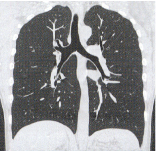

コロナル断面 -